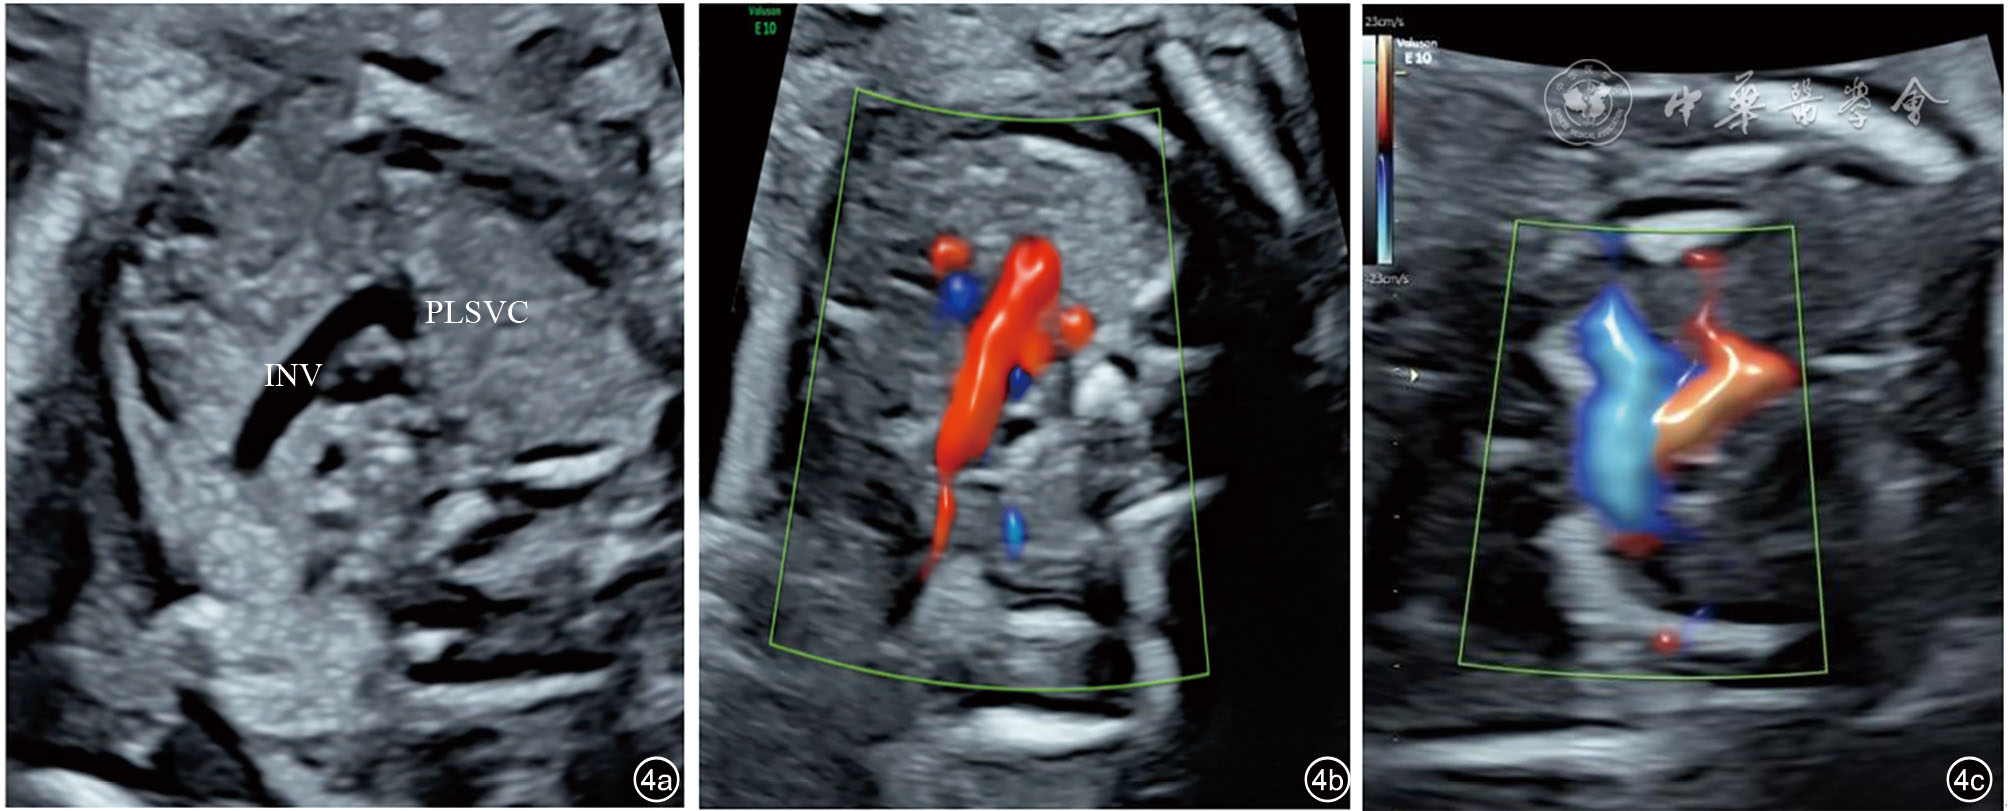

图4 永存左上腔静脉合并右上腔静脉缺如胎儿与正常胎儿无名静脉切面超声图像。图a、b为永存左上腔静脉合并右上腔静脉缺如胎儿二维超声及彩色多普勒血流图像,无名静脉切面显示血流反向(红色)汇入左上腔静脉;图c显示同一体位正常胎儿无名静脉(蓝色)汇入右上腔静脉 注:INV为无名静脉;PLSVC为永存左上腔静脉